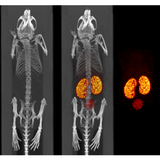

The X-CUBE is our high throughput CT “work horse”. It allows for fast whole body mouse and rat CT imaging at extremely low dose and excellent soft tissue contrast.

Light weighted thanks to a self-shielded imaging unit it is a truly mobile in vivo scanner. Advanced workflows such as gated and dynamic contrast enhanced imaging can be achieved in a functional and integrated set up. Our iterative reconstruction techniques are available in standard as well as expert user mode. Intuitive and wireless acquisition software combined with our multimodal small animal bed allow for easy and modular multimodal imaging along with the γ-CUBE (SPECT) and β-CUBE (PET).